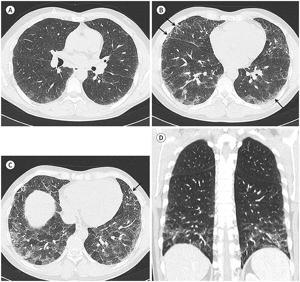

- 진단: 흉부 CT, 폐 기능 검사, 조직 생검 등을 활용

- 고해상도 흉부 CT와 폐조직 검사, 다양한 감별진단(자가면역질환, 약물, 환경성 노출 가능성 배제) 과정이 필요합니다.